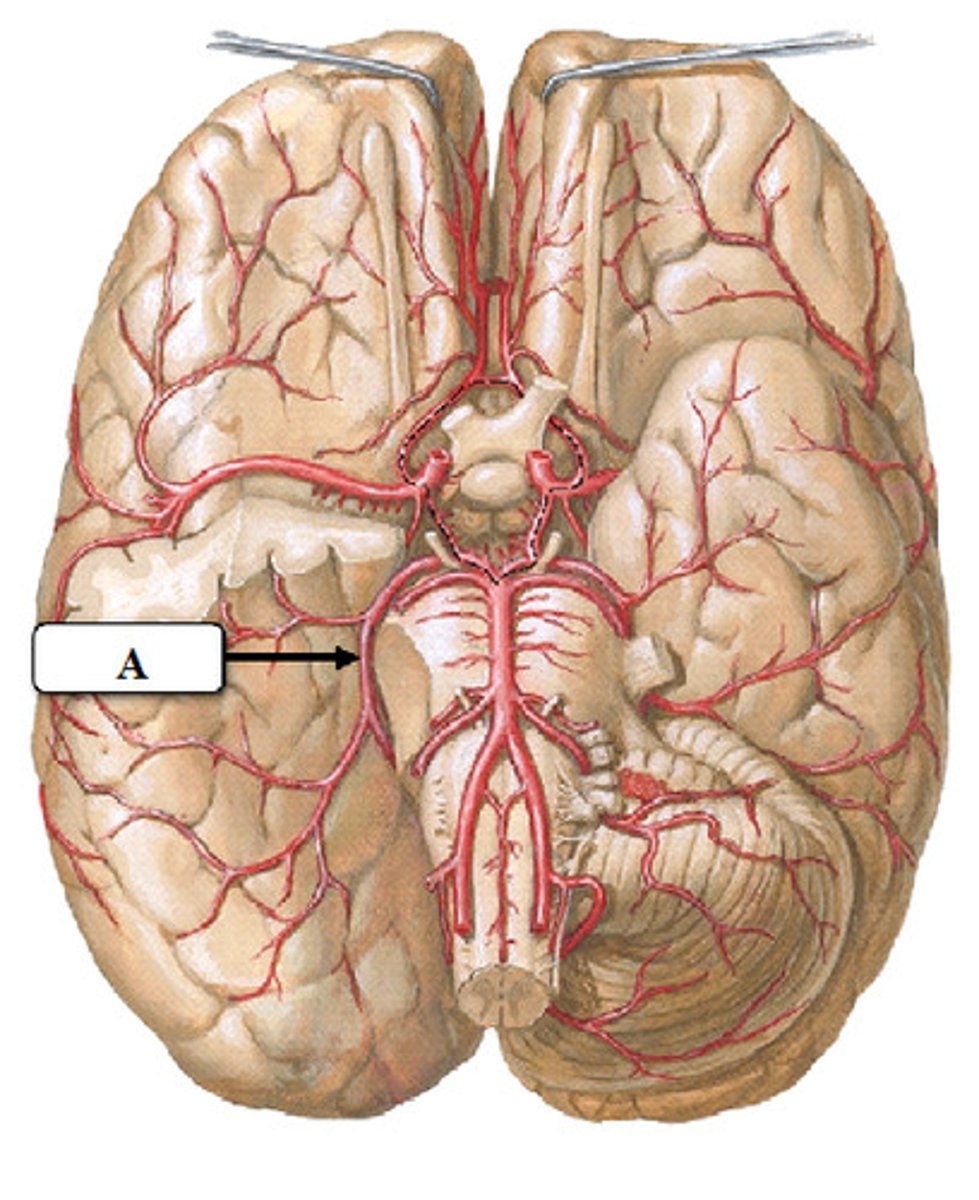

vertebral arteries

Arteries that ascend the vertebrae, enter the base of the skull, and join together to form the basilar artery. Travel through foramen magnum to reach the pons.

internal carotid arteries

this artery branches off the common carotid arteries, travel up into the skull through the carotid canal, and then divide to form the anterior and middle cerebral arteries.

anterior cerebral arteries

two large arteries, arising from the internal carotid arteries. Travels anteromedially to the median longitudinal fissure where it supplies the superior and medial aspects of the frontal and parietal lobes.

middle cerebral arteries

two large arteries, arising from the internal carotid arteries. Dives into the lateral fissure to travel to the lateral aspect of the brain, where it supplies the majority of the temporal lobe and a large portion of the frontal and parietal lobes.

posterior cerebral arteries

Two large arteries, arising from the basilar artery, that supply the posterior aspect of the brain, including the occipital lobes, as well as the inferior portion of the temporal lobes.

anterior communicating artery

Connects the two anterior cerebral arteries before they enter the median longitudinal fissure

posterior communicating artery

small arteries that connect the posterior cerebral and internal carotid arteries.

basilar artery

arises from the vertebral arteries and runs along the pons before dividing into posterior cerebral arteries.